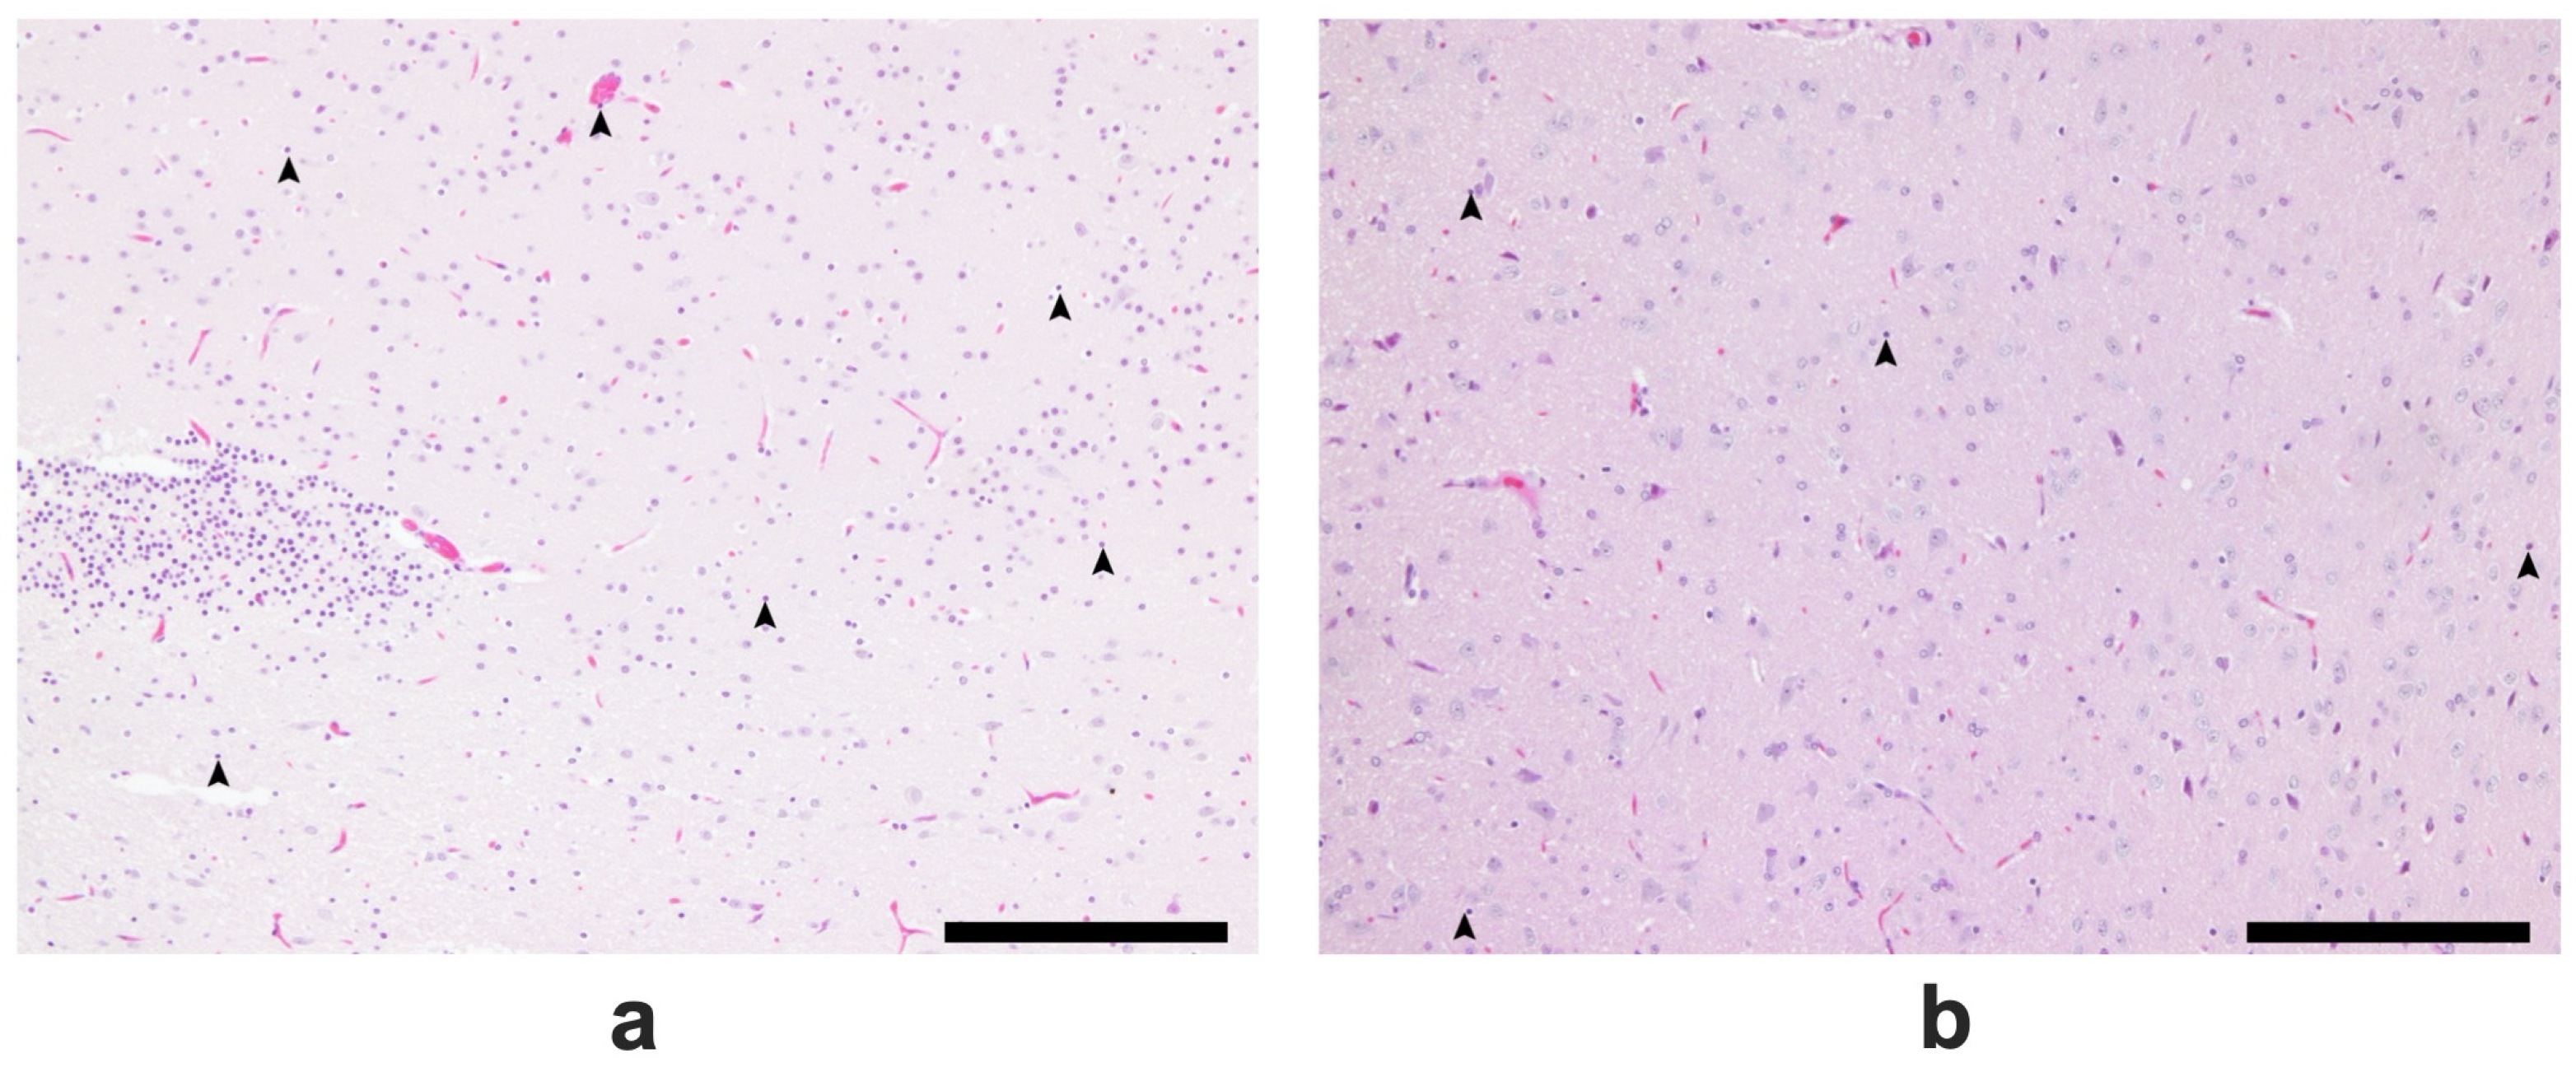

2.5. Results of the Histopathological Analysis of Brain Tissues

4.4.5. Histopathological Analysis of Brain Tissues